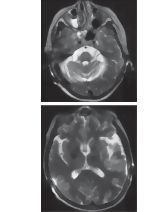

Diagnosis of Multiple System Atrophy